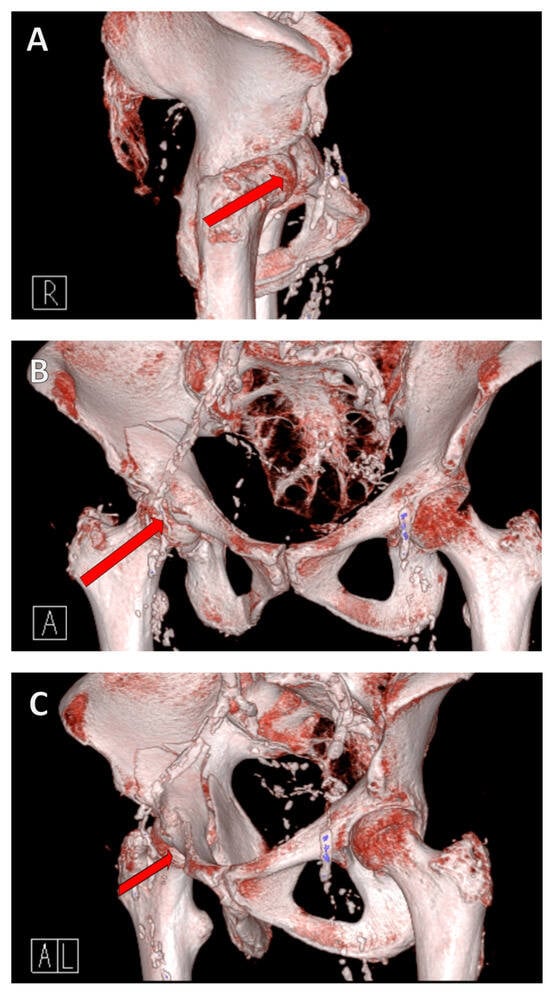

For the modified Stoppa approach, the patient is placed in the supine position with the hands extended on either side of the body (Figure 4A). Due to the positioning, the X-ray image converter can be used intraoperatively for the standard anterior–posterior (AP), ala, and obturator images, and, depending on the inclination of the image converter, allows the examination of screws positioned next to the joint [27]. After sterile covering of the patient, a Pfannenstil incision is made, although vertical incisions are also possible. The difference between the incisions is currently the subject of scientific discussion, with a vertical incision being associated with a lower infection rate [42,43].

It is recommended to use femoral protrusion to facilitate anatomical reduction of the acetabulum. This can be achieved using a Schanz screw, which is inserted laterally into the femoral neck and, in the best case, connected to Martin’s arm retractor, allowing the lateral traction to be held permanently (Figure 4B–F).

The correct position of the screws should be checked intraoperatively by X-ray control in the ala/obturator and AP view, which confirms the extra-articular position of the screws (Figure 6). The infra-acetabular screw can be scored in its extra-articular position, confirming the correct position outside the hip joint. Postoperatively, the correct position should be confirmed by CT.

Open reduction and internal fixation (ORIF) of the acetabular fracture is then performed. The correct position of the screws is checked intraoperatively using an X-ray C-arm (Figure 6).

Figure 6. Intraoperative X-ray control. It is important to position the patient correctly; a carbon table should be used, and this should be moved out as far as possible so that there is plenty of space to swivel the X-ray C-arm (A). The correct screw position is checked in different planes. Here, the infra-acetabular screw is in the correct position, i.e., not through the joint (BD).